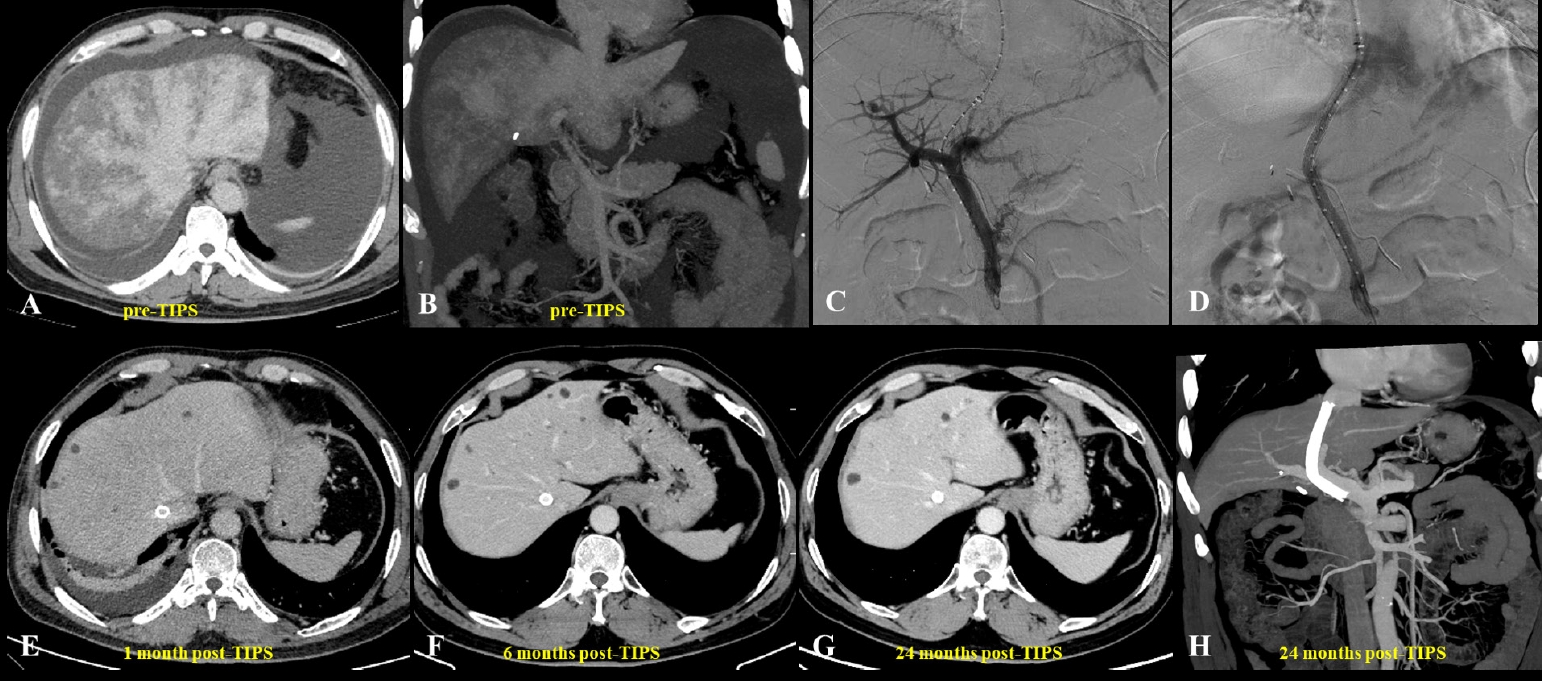

Fig. 2.A 23-year-old woman presented with pyrrolizidine alkaloid–induced hepatic sinusoidal obstruction syndrome following ingestion of oral weight-loss medications. (A) Pre–transjugular intrahepatic portosystemic shunt (TIPS) computed tomography (CT) (portal venous phase) demonstrated heterogeneous, patchy hepatic enhancement with multiple regenerative nodules (yellow arrow), accompanied by massive ascites and bilateral pleural effusions. (B) Histopathological analysis from a transjugular liver biopsy revealed focal hepatic atrophy, marked sinusoidal dilatation, and hepatocellular cholestasis, consistent with hepatic venous outflow obstruction. Immunohistochemical staining was negative for hepatitis B surface antigen, hepatitis B core antigen, diastase-periodic acid-Schiff, and periodic acid-Schiff, while showing positivity for cytokeratin 7 (biliary epithelium), reticulin, and Masson’s trichrome (indicating underlying fibrosis) (H&E, ×400). (C) Due to the diminished caliber (slenderness) of the portal vein, percutaneous transhepatic balloon-assisted TIPS placement was performed. Initial portal venography confirmed narrowing of the intrahepatic portal branches, stagnant portal flow, and the presence of prominent esophagogastric varices. (D) Post-TIPS venography demonstrated a widely patent shunt with unobstructed portal venous return and successful decompression of the varices. (E-H) Follow-up contrast-enhanced CT scans (venous phase) obtained at 1 month (E), 6 months (F), 12 months (G), and up to 72 months (H) post-TIPS demonstrated persistent heterogeneous enhancement and intrahepatic nodules (yellow arrows).

TIPS has emerged as an important therapeutic option for PA-HSOS patients with refractory PH or ascites, and although it has no specific contraindications for treatment, guidelines recommend considering it for patients with ineffective medical therapy, highlighting the importance of individualized assessment [

15]. Studies have shown that ascites and pleural effusions can markedly improve within a short period after TIPS placement, with previously obstructed hepatic veins often regaining patency in the short term when combined with AT (

Figs. 1,

2) [

10,

52]. Various studies have confirmed the safety and efficacy of TIPS in managing PA-HSOS (